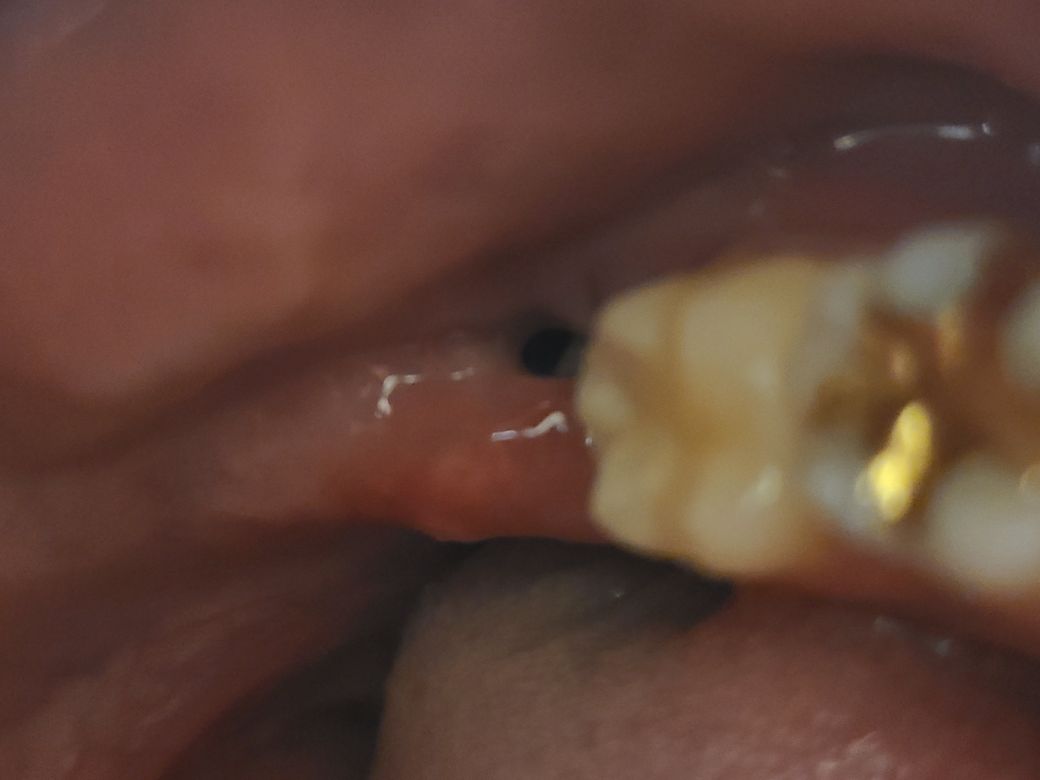

사랑니 발치후 주변잇몸부음(사진)

발치한지 4일차이고 원래 약간 턱신경쪽과 가까워서 전문병원에서 발치진행했습니다. 아프진않아서 진통제는 안먹고있는데 꼬멘상태인데 주변잇몸이 많이부은게 느껴지는데 정상적인 치유과정인지 궁금해요

따로 문제는 없겠죠?

보이시는 뺀 곳 좌측이 많이 부었어요

• 1번 째 사진